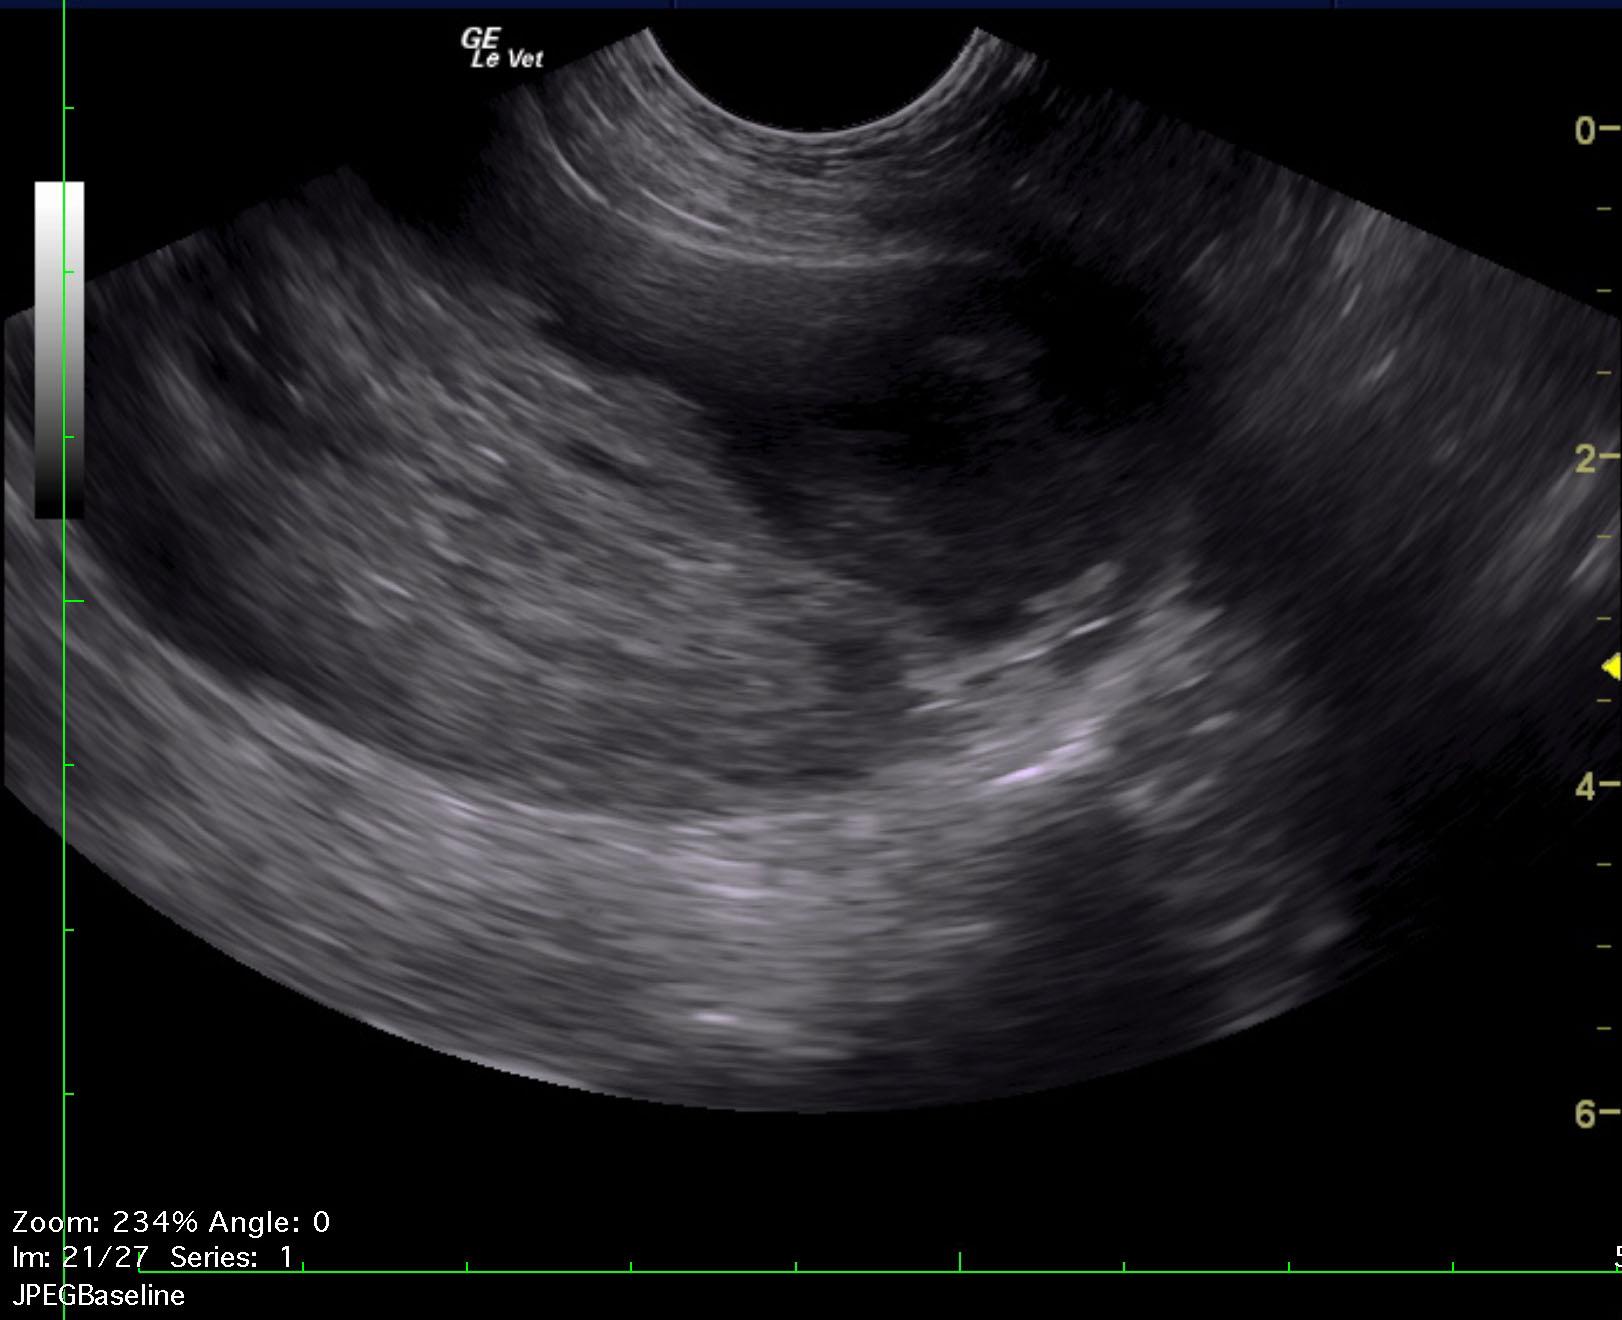

A 10-year-old intact male Komodor with a history of bleeding from the penis was presented recumbent and dyspneic. Abnormalities on CBC and serum biochemistry were leukocytosis, band neutrophilia, monocytosis, azotemia, mild hyperglobulinemia, mildly elevated liver enzyme activity and hyperbilirubinemia.